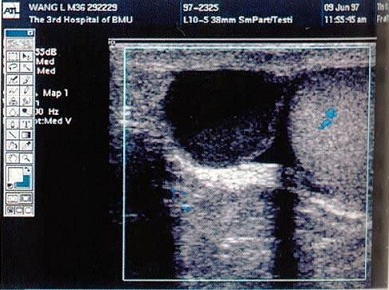

60、单项选择题

患者男,21岁,发现睾丸无痛肿块,局部不规则,结合超声图像,最可能的诊断是()。

A.精原细胞瘤

B.睾丸畸胎瘤

C.精母细胞瘤

D.睾丸腺癌

E.睾丸囊肿